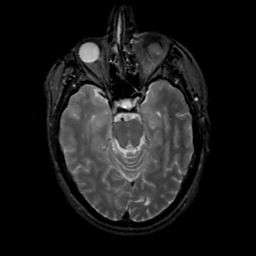

MR Study #16, June 23, 1991 -- Slice #18